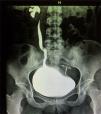

Presenta sintomatología del tracto urinario inferior 90 días antes de su ingreso, caracterizado por síntomas de vaciamiento vesical incompleto, intermitencia miccional, pujo y tenesmo vesical. Al realizar un gran esfuerzo para vaciamiento vesical presentó retención aguda de orina y aparición súbita de una tumoración a nivel vulvar, la cual persistió durante 20h, por lo que decide acudir a urgencias. En la exploración física: paciente con facies dolorosa, dolor abdominal bajo con globo vesical palpable, y a nivel vulvar un tumor de 5×7×3 cm de diámetro, color rojo oscuro de aspecto isquémico, doloroso a la movilización, de consistencia ahulada y renitente que protruye de la uretra. Bajo anestesia regional se redujo manualmente y se colocó sonda Foley No. 16Fr, obteniendo orina residual turbia, concentrada y fétida (fig. 1).

Se hospitalizó para manejo médico con antibiótico, antiespasmódico, anticolinérgico y para realizar urotomografía, el cual demostró ureterocele gigante derecho sin alteraciones anatómicas anexas a esta enfermedad. La paciente evolucionó satisfactoriamente, por lo que fue egresada con su sonda Foley, y 8 días después se realizó cistoscopia encontrando destechamiento isquémico de la pared anterior del ureterocele derecho (fig. 2), uréter contralateral normal (fig. 3) y reflujo vesicoureteral grado IV derecho que fue corroborado por cistograma miccional (figs. 4 y 5), se le realizó reimplante ureteral derecho tipo Cohen, con colocación de catéter doble-J ipsilateral, y un mes después se retiró dicho catéter. La paciente a los 3 meses se encontraba asintomática, y el cultivo y examen general de orina eran normales.